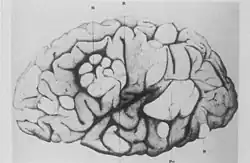

A side profile sketch of a brain, with parts indicated by a letter code. The normal convolutions of the brain are distorted in these areas, forming lumps or thickened folds.

Cerebral tuberous sclerosis showing sclerotic, hypertrophic circumvolutions.

French neurologist Désiré-Magloire Bourneville had a chance encounter with the disease that would bear his name. He was working as an unofficial assistant to Jean Martin Charcot at La Salpêtrière.[10] While substituting for his teacher, Louis J.F. Delasiauve,[12] he attended to Marie, a 15-year-old girl with psychomotor retardation, epilepsy and a "confluent vascular-papulous eruption of the nose, the cheeks and forehead". She had a history of seizures since infancy and was taken to the children's hospital aged three and declared a hopeless case. She had learning difficulties and could neither walk nor talk. While under Bourneville's care, Marie had an ever-increasing number of seizures, which came in clusters. She was treated with quinquina, bromide of camphor, amyl nitrite, and the application of leeches behind the ears. On 7 May 1879 Marie died in her hospital bed. The post-mortem examination disclosed hard, dense tubers in the cerebral convolutions, which Bourneville named Sclérose tubéreuse des circonvolutions cérébrales. He concluded they were the source (focus) of her seizures. In addition, whitish hard masses, one "the size of a walnut", were found in both kidneys.[13]

Bourneville and Édouard Brissaud examined a four-year-old boy at La Bicêtre. As before, this patient had cortical tubers, epilepsy and learning difficulties. In addition he had a heart murmur and, on post-mortem examination, had tiny hard tumours in the ventricle walls in the brain (subependymal nodules) and small tumours in the kidneys (angiomyolipomas).[16]